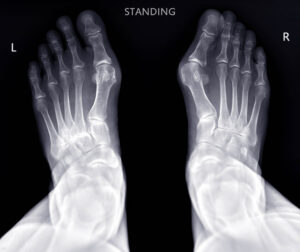

What digital X-rays show well:

• Bones and fractures

• Joint alignment and arthritis

• Dense objects (metal, swallowed items, kidney stones)

• Air-filled structures like lungs

• Heart size and shape

• Certain lung conditions